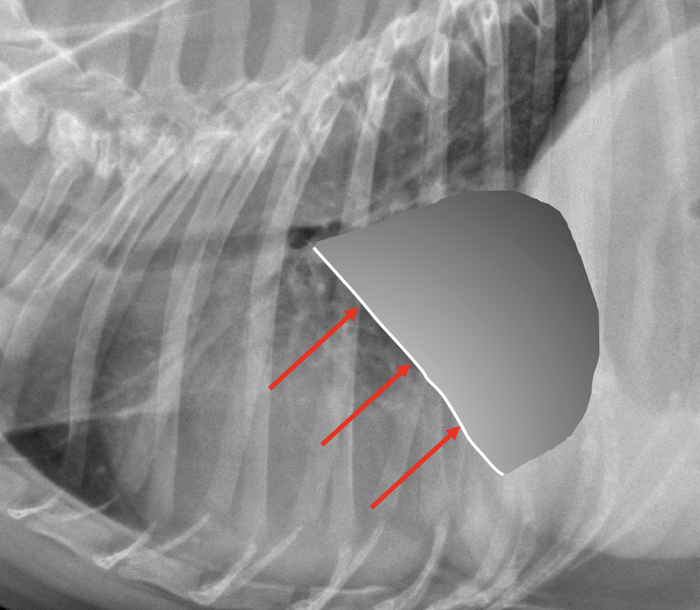

Lung Pattern?

Pneumothorax *Arrows = atelectasis*